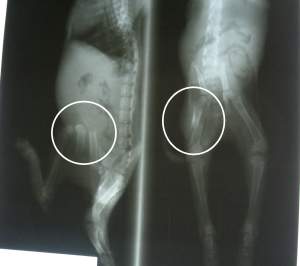

Manche Katzen kommen in einem furchtbaren Zustand in die Auffang- oder Tötungsstationen. So auch Nana. Nana wurde in diesem Zustand gefunden. Sie hätte auf der Straße, wo sie ausgesetzt wurde, nicht mehr lange überlebt. Wahrscheinlich wurde sie von einem Hund gebissen. Am Hals hat sie ein riesigen Abszess. Die Augen sind total entzündet. Sie ist voll mit Flöhen. Als ob das alles nicht schon genug wäre, hat sie auch noch einen gebrochenen Oberschenkel. Nana wird nun erstmal richtig gepäppelt, um wieder zu Kräften zu kommen.